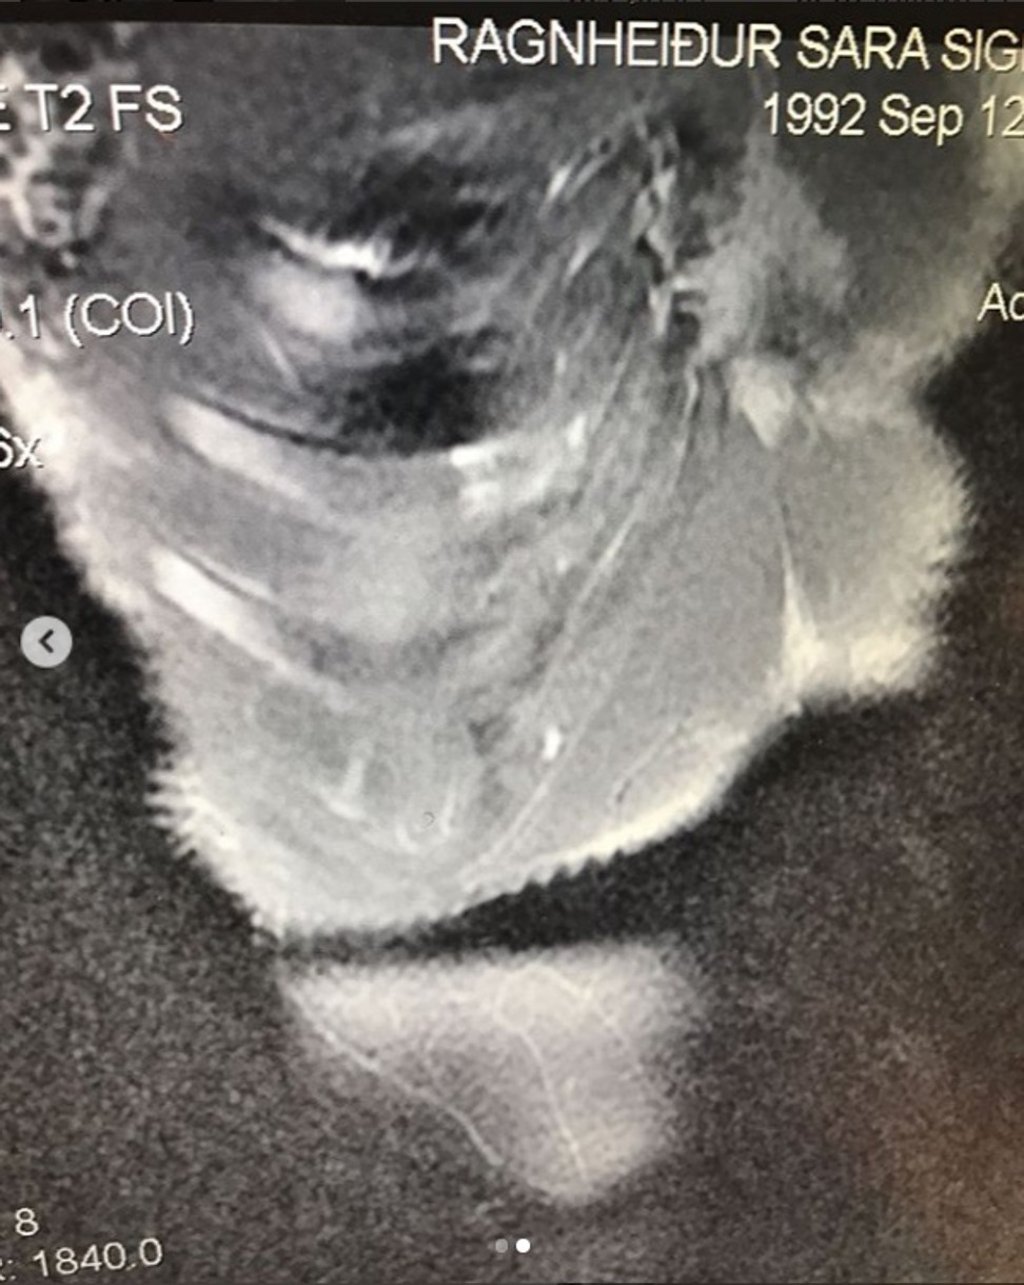

CrossFit Games 2018: Sara Sigmundsdottir reveals broken rib forced her to quit as MRI scan brings ‘dreaded confirmation’

“Today I got an MRI and a dreaded confirmation that my 9th rib is in fact broken. The good news [is] that it is healing nicely and I might be only 4-6 more weeks from being able to resume 100 per cent training.